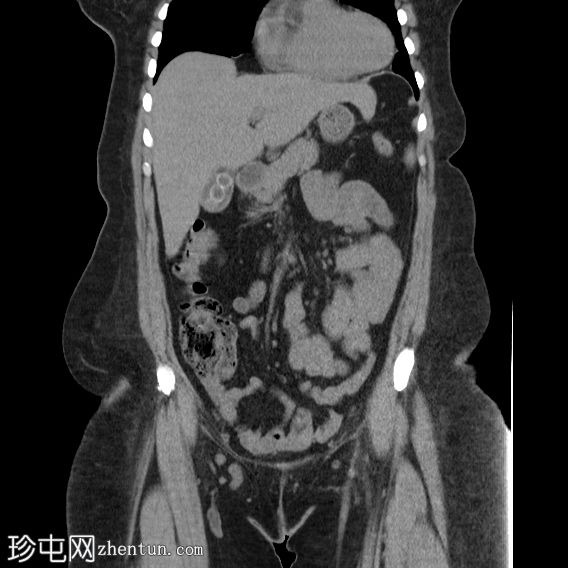

轴位

平扫

胆囊内可见多发大小不一的多面环状钙化胆结石。胆总管直径处于正常上限。胆总管内未见其他结石。

右侧肾中盏可见一非梗阻性结石(10.5 mm),CT值较高(900–1000 HU)。

钙化胆囊结石相对于胆汁呈高密度,因此是唯一能在CT图像上清晰显示的结石类型。在CT图像上,大部分胆固醇结石相对于胆汁呈低密度,而其他类型的胆结石与胆汁呈等密度,这些结石在CT图像上可能无法清晰显示。

右肾中盏可见高密度肾结石(900–1000 HU),提示为含钙硬结石,可能为草酸钙一水合物。